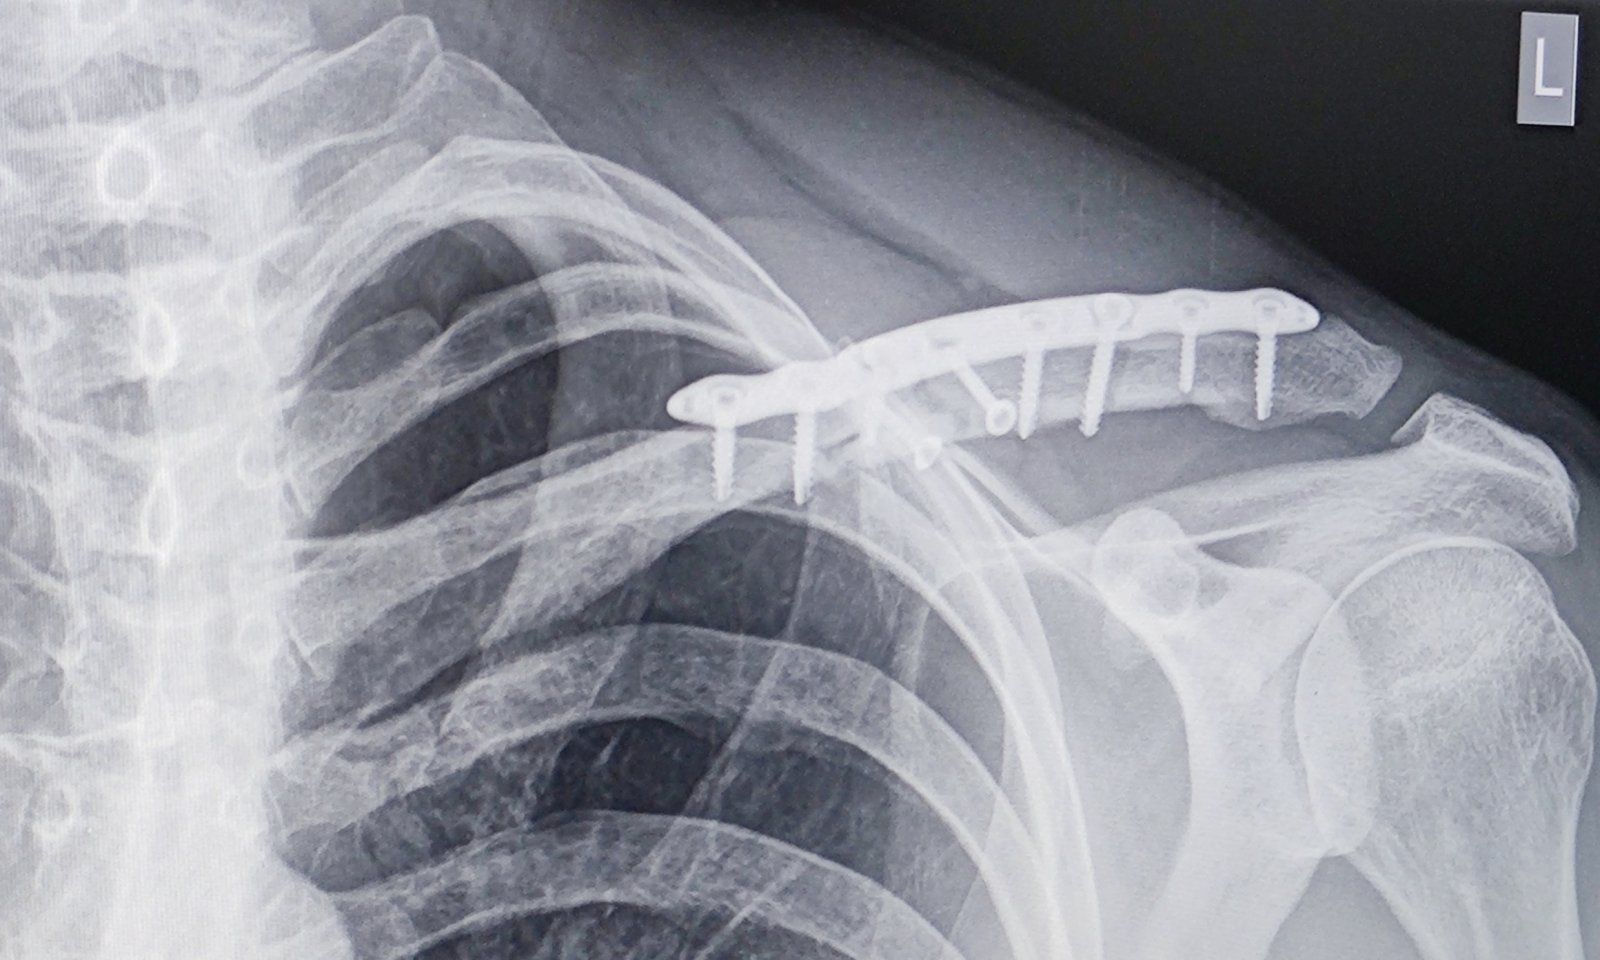

Oh ganz schön viel Metall 😳 Auch Dir weiterhin gute Besserung 💪🏻